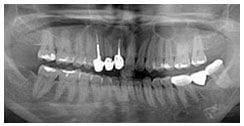

X 光片

術前X光片